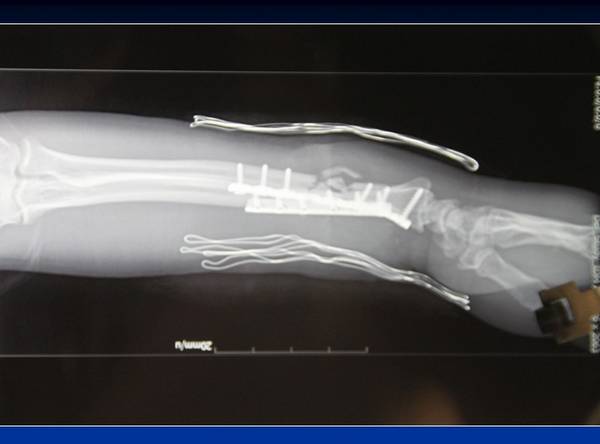

经典病例

省立医院王德华主任作品

取对侧头静脉桥接桡动脉

取胫后动脉皮瓣,串联尺动脉